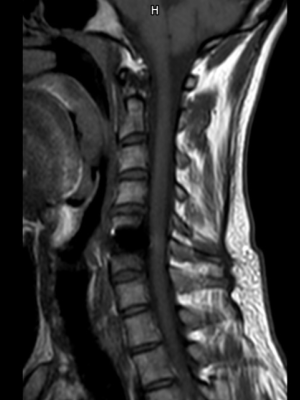

El recubrimiento de Diamolith (DLC) de las placas de titanio reduce los artefactos en la RM, lo cual permite un mejor seguimiento postoperatorio.